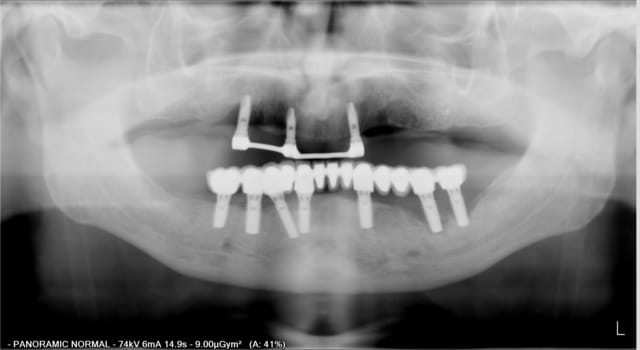

en haut,4 implant ont été posé en postextractionnel en vue d'une barre + stellite pano1.

L' implant en 21 à été perdu de façon précoce (avant mise en charge), mais la prothèse a tout de même été réalisée

en bas extraction du bloc antérieur + MCI (37 a été conservée)puis prothèse scellée au fujiplus sur pilier usiné.

Lors du controle à 1 an, on voit déjà une lésion autour de l'implant en 13.

Désolé mais les pano ne se sont pas mise dans l'ordre chronologique

En fait la plus récente est celle de gauche, et effectivement sur la plus a droite le patient a bougé